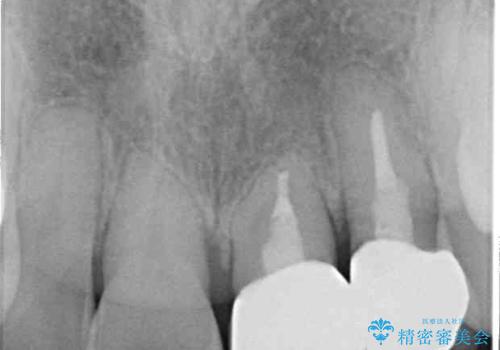

前歯が内側に倒れ込む力がかかり、正常な歯ぎしりもできないため、非常に負担のかかりやすい咬み合わせでした。

矯正治療中に上顎前歯が下顎前歯を乗り越える際は、前歯でしか咬めない状況が続くため、食事など不便を感じましたが、治療後には前歯の痛みもなくなり、安定した咬み合わせとなりました。